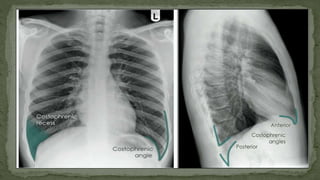

5. COSTOPHRENIC ANGLE AND RECESS

• The costophrenic recesses are formed by hemidiaphragms

and chest wall.

• They contain the rim of the lung bases which lie over the

dome of each hemidiaphragm.

• These angles are known as the costophrenic angles.

• Costophrenic angles should form acute angles that are

sharp to the point.

Pleural effussion left

?

Pleural effussion right